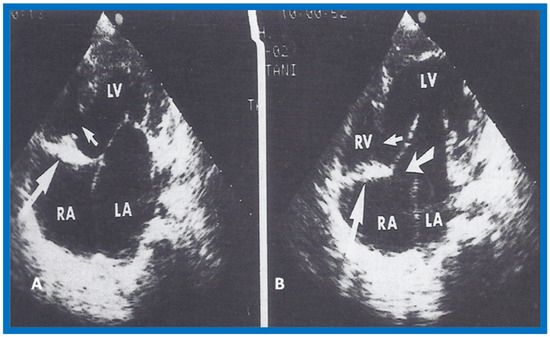

14. Echocardiographic Demonstration of Atrioventricular Type of Tricuspid Atresia

The author reported on the clinical, radiographic, ECG, echocardiographic and hemodynamic features of a rare case of common atrioventricular canal (currently called atrioventricular septal defect) mimicking tricuspid atresia in an eight-year-old child [15]. The clinical, radiographic and ECG characteristics were similar to those of classic tricuspid atresia. Hemodynamic data secured at cardiac catheterization were also similar to those seen with tricuspid atresia. A two-dimensional echocardiogram demonstrated an ostium primum atrial septal defect with a common atrioventricular valve and a small RV (Figure 50a,b); the entry into the RV appeared to be occluded by a leaflet of the common atrioventricular valve. Left ventricular cineangiogram in postero-anterior view demonstrated “gooseneck” deformity, similar to that seen in atrioventricular canal defects [15]. However, right atrial angiography resulted in direct emptying of the contrast material into the left ventricle via an ostium primum atrial septal defect (Figure 51). The floor of the right atrium seemed to be formed by a leaflet of the common atrioventricular valve (Figure 51). Thus, the two-dimensional echocardiographic and right atrial cineangiographic features appeared to be distinctive, and could be utilized to distinguish this anomaly from other varieties of tricuspid atresia.

Figure 50.

Selected two-dimensional, subcostal, four-chamber echocardiographic frames with an open (a) and closed (b) atrioventricular valve. Line drawings on the right of a and b are made for greater clarity and for labeling. A large ostium primum atrial septal defect (10 ASD) is shown in a. When the large atrioventricular valve leaflet is open (a), it completely closes the right ventricle (RV) from the right atrium (RA) and ventricular septal defect (VSD) and allows emptying of blood from both atria into the left ventricle (LV). When atrioventricular valve leaflet is closed (b), it continues to occlude the RV from the RA while allowing the VSD to freely communicate between RV and LV. Ap, Apex; AtTV, atretic tricuspid valve; Ba, base; L, left; LA, left atrium; R, right. Reproduced from Rao P.S. [15].

The reported anomaly is definitely different from classic tricuspid atresia, but has physiologic effects similar to classic tricuspid atresia. A detailed review of the literature at that time suggested that this anomaly is extremely rare, with only one brief mention of a similar case by Van Praagh by that time [50]. Evaluation of crux cordis (Figure 54) on two-dimensional echocardiogram (subcostal four-chamber view) may help to distinguish these anomalies from each other. In muscular type of tricuspid atresia, a dense band of echoes is seen where the normal tricuspid valve should be (Figure 52a). In membranous types of tricuspid atresia, a thin membrane is seen instead (Figure 52b). In both types, the anterior leaflet of the detectable atrioventricular valve is attached to the left side of interatrial septum (Figure 52a,b). In the atrioventricular canal type of tricuspid atresia, the crux cordis is abnormal and cannot be identified, and a large atrioventricular valve leaflet occludes the entry of the RA into the RV (Figure 52c). It was concluded that two-dimensional echocardiographic and angiographic features help differentiate atrioventricular canal type of tricuspid atresia from classic tricuspid atresia cases [15].

Figure 52.

Line drawings demonstrating two dimensional echocardiographic appearances in subcostal four-chamber view of the muscular (a), membranous (b), and atrioventricular canal (c) variants of tricuspid atresia. (a) The atretic tricuspid valve is represented by a thick band of echoes between the right atrium (RA) and the small right ventricle (RV) in the muscular type. (b) The tricuspid valve is represented by a thin line in the membranous type. Note that crux of the heart (arrows in a and b) is well seen in both these types (a and b). The attachment of the anterior leaflet of the detectable atrioventricular valve to the left side of the interatrial septum is evident. (c) In the atrioventricular canal type of tricuspid atresia, the anterior leaflet of the detectable atrioventricular canal is attached to the anterior wall of the heart, occluding the right ventricle from the right atrium and allowing blood exit of both atria into the left ventricle (LV). Crux cordis and the atrioventricular portion of the interventricular septum are not seen. Reproduced from Rao P.S. [15,40].